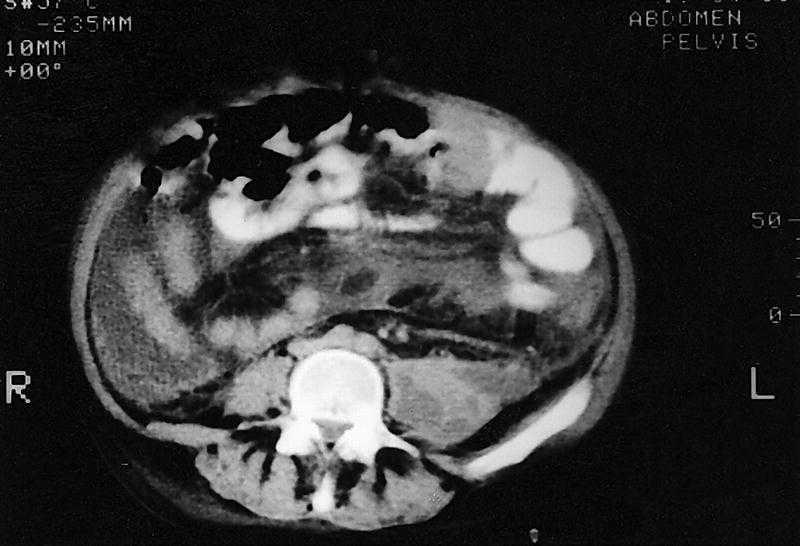

En la tomografía computarizada (TC) abdominopélvica se visualiza un absceso a lo largo del psoas izquierdo que empieza a la altura del hilio renal izquierdo hacia pelvis con imágenes de densidad líquida en su interior, sin datos de osteomielitis lumbar (fig. 2). Se colocó un catéter de drenaje, aislándose en los cultivos Citrobacter freundi y Enterobacter cloacae.

Fig. 2.